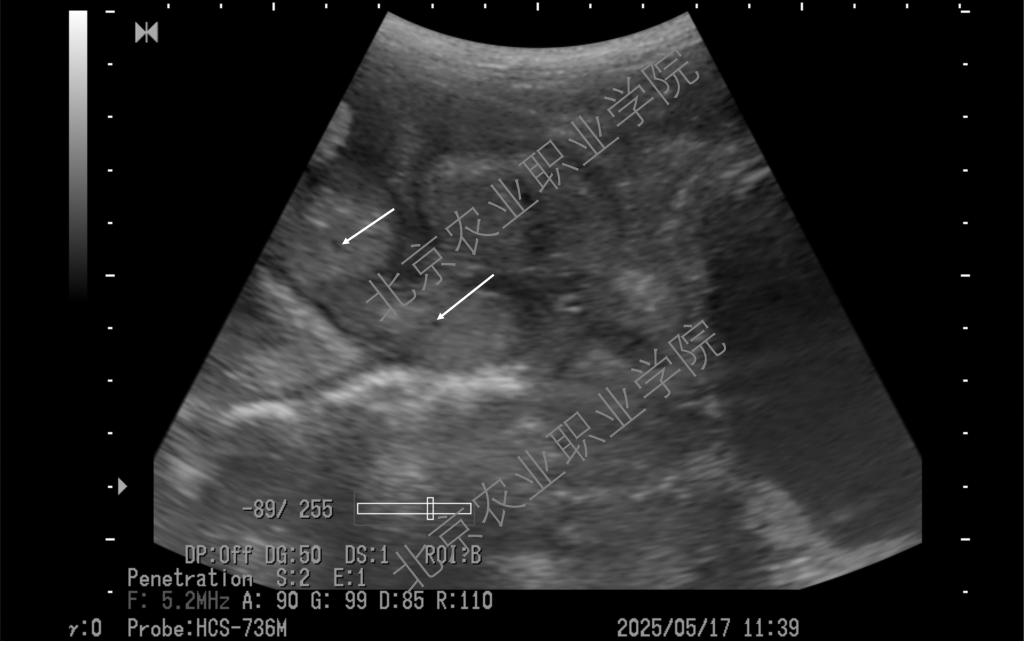

近日,受北京伟杰信生物科技有限公司邀请,动物科技学院兽医超声技术团队为该公司“母猪妊娠21天超声检查技术操作规范”项目提供了重要的技术支撑,并取得重大进展。团队首席专家姜晨副教授梳理了母猪不同体位超声扫查的方法,以便技术人员在不改变母猪体位的情况下做出准确诊断,最大程度上降低怀孕母猪不必要的应激。

近年来,我院姜晨副教授领衔的兽医超声技术团队积极推广超声影像技术在多种动物临床中的应用,并取得一系列技术成果。团队持续探索母猪孕早期超声检查的边界,目前最早可在排卵后第9天确认是否怀孕(可见直径约1mm的卵囊液)。此超声检查技术已达到国际前沿水平,为打开母猪孕初相关的科学研究之门提供了一把金钥匙。